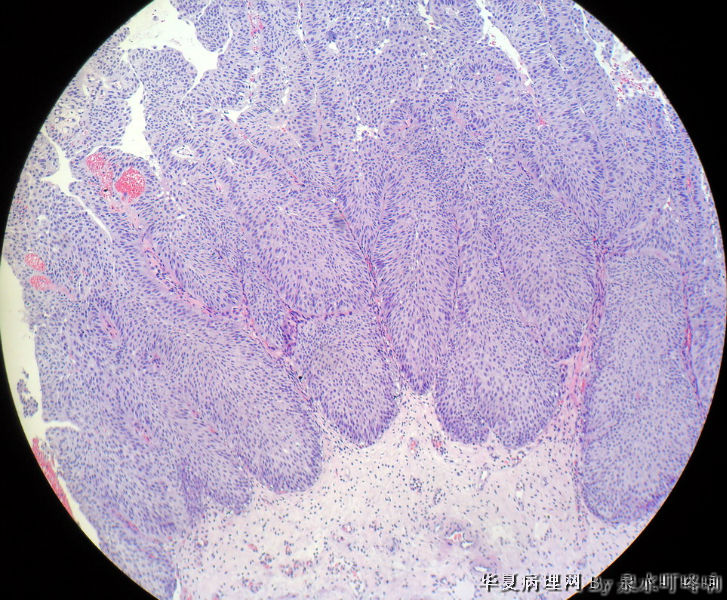

膀胱肿物

膀胱肿物图1

名称:图1

描述:1

男,76岁,血尿一个月,发现膀胱肿物,行切除术,肿物位于右侧膀胱后外侧壁,约1.5×1.5×1.5厘米。

大体:灰白肿物一个,大小约2×1.1×0.9厘米,切面灰白,质中。

尿路上皮癌,低级别。

低级别非浸润性乳头状尿路上皮癌

(膀胱)非浸润性乳头状尿路上皮癌,低级别

低级别尿路上皮癌。至于浸润的问题还请楼主仔细观察切片,总感觉那种推进式的生长模式有浸润的嫌疑,临床上浸润与否治疗方式是不一样的。

Dx: High grade papillary urothelial carcinoma because: 1. nuclear chromasia (fig 13) and coarse chromatin. 2, almost all nuclei have prominent  nucleoli. 3, Nuclear pleomorphism (some nuclei are three times larger than smaller ones). 4. Nuclear membrane irregularity. 5. mitosis can be seen far away from the basement membrane. 6. a good portion of the neoplastic cells loss orientation that should be perpendicular to the basement membrane. 7. Low power view shows papillary branching and fusion. 8. patient's age

However, this should be the low end of the spectrum of high grade urothelial carcinoma. Careful search might reveal some focal microinvasion.or urothelial carcinoma in situ.